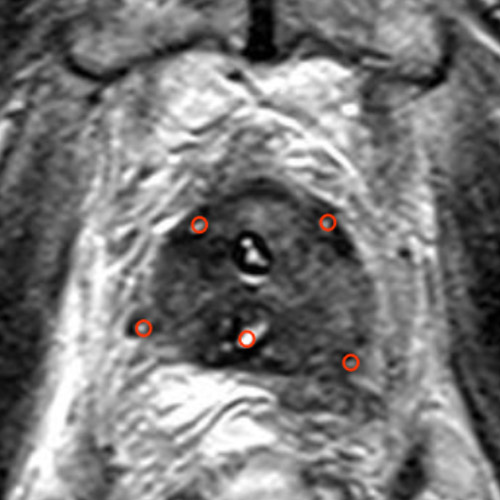

Die erste Bedingung wird durch eine Multiparameter-MRT-Untersuchung, eine 3D-Biopsie und, wenn nötig, weitere Verfahren erfüllt. Die zweite Bedingung wird durch einen minimalinvasiven Eingriff unter Vollnarkose erfüllt. Dabei werden sterile Nadeln mit variabler Expositionslänge eingeführt. „Expositionslänge“ bezieht sich auf den Bereich der Nadel, der das Gewebe mit elektrischem Strom in Kontakt bringt. Mit diesem Verfahren haben wir bereits seit 2011 Erfahrung und haben weltweit die meisten Prostatabehandlungen durchgeführt. Damit gehören wir zu den führenden Experten weltweit, während andere Kliniken gerade erst am Anfang stehen.

Die 3D-Aufnahmen aus der MRT erhalten durch eine 3D-Sättigungsbiopsie noch eine weitere Ebene. Wir sind auf beide Verfahren spezialisiert. Beide sind erforderlich, um die Genauigkeit bei der Diagnostik zu erzielen, die notwendig ist, damit die NanoKnife-Behandlung wirksam durchgeführt werden kann.

Haben unsere Ärzte und Physiker den Zielbereich einmal mit Hilfe der MRT-Querschnittsbilder bestimmt und ihn, wenn nötig, mittels von uns entwickelter 3D-Simulationen vorab berechnet, wird der Zielbereich gespeichert und am Tag der Operation auf den Operationsmonitor übertragen.

Für die Behandlung der Prostata werden die Nadeln transperineal, also durch den Damm (den Bereich zwischen Genitalien und Anus), eingeführt. Ein endorektaler Ultraschall hilft bei der Platzierung. Hierbei spielt Erfahrung eine entscheidende Rolle. Bereits zwei Nadeln stellen hohe Anforderungen an das räumliche Vorstellungsvermögen des Operateurs. Platzierungen mit vielen Nadeln sind eine extrem große Herausforderung. Das liegt daran, dass die Prostata ein relativ kleines Organ mit einer komplexen Geometrie ist, umgeben von vielen sensiblen anatomischen Strukturen. Darüber hinaus sind die Positionierungsmöglichkeiten der Nadeln sehr eingeschränkt. Dieser Prozess kann mitunter mehreren Stunden dauern, obwohl uns hier im VITUS Prostata Center Computerprogramme dabei unterstützen, die perfekte Platzierung zu erreichen.